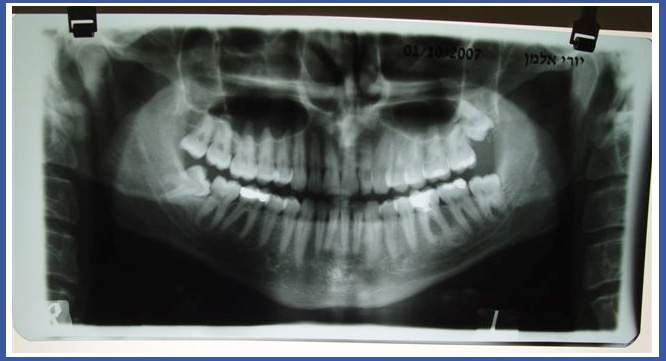

5.צילום פנורמי:

זהו צילום שנעשה במכון רנטגן ומכיל את שתי הלסתות ביחד. צילום פנורמי מראה לרופא את האנטומיה של הלסתות והשיניים בדו מימד. בצילום נראית האנטומיה של חלק מהגולגולת, החל ברצפת העין, מערות האף הלסתות, מפרקי הלסת ועוד.

הצילום נעשה בדרך כלל לפני עקירות שיני בינה- לצורך בדיקת קרבת השן לתעלת העצב, כמו כן לפני השתלות שיניים כאמצעי אבחנתי ראשוני הנותן לרופא מידע כללי לגבי מערות האף, גובה העצם ומיקום העצב. במקרים בהם קיימת פתולוגיה כלשהי (גידול, נגע, דלקת נרחבת) הצילום הוא אמצעי אבחנתי ראשוני מצויין.